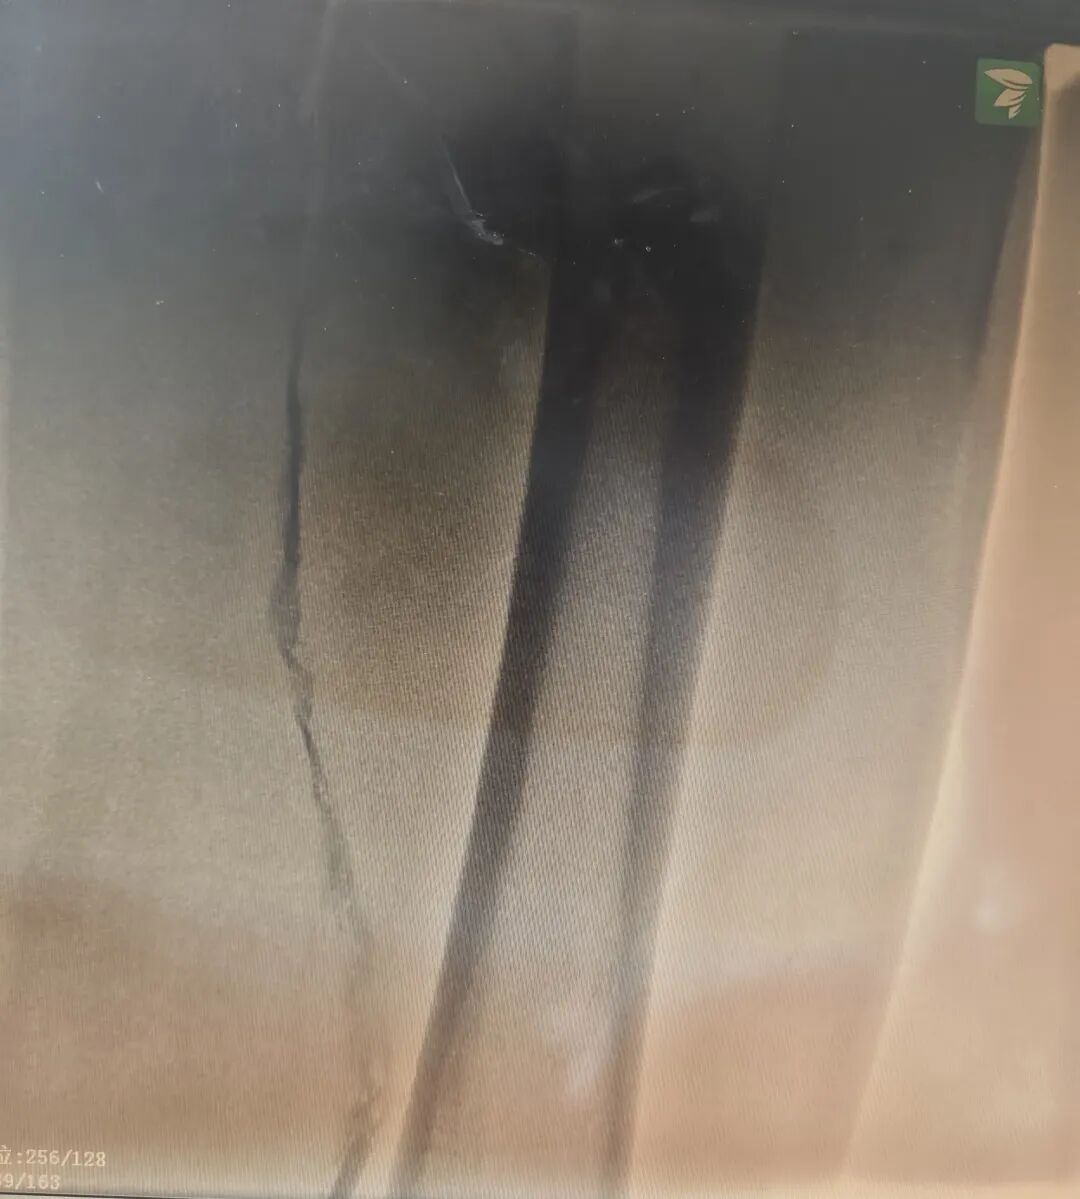

术前造影

术中,挑战如期而至:经足背留置针造影提示,患者左侧腘静脉、股浅静脉、腓静脉、胫后静脉、颈前静脉均被血栓闭塞,情况比预想的更为复杂。